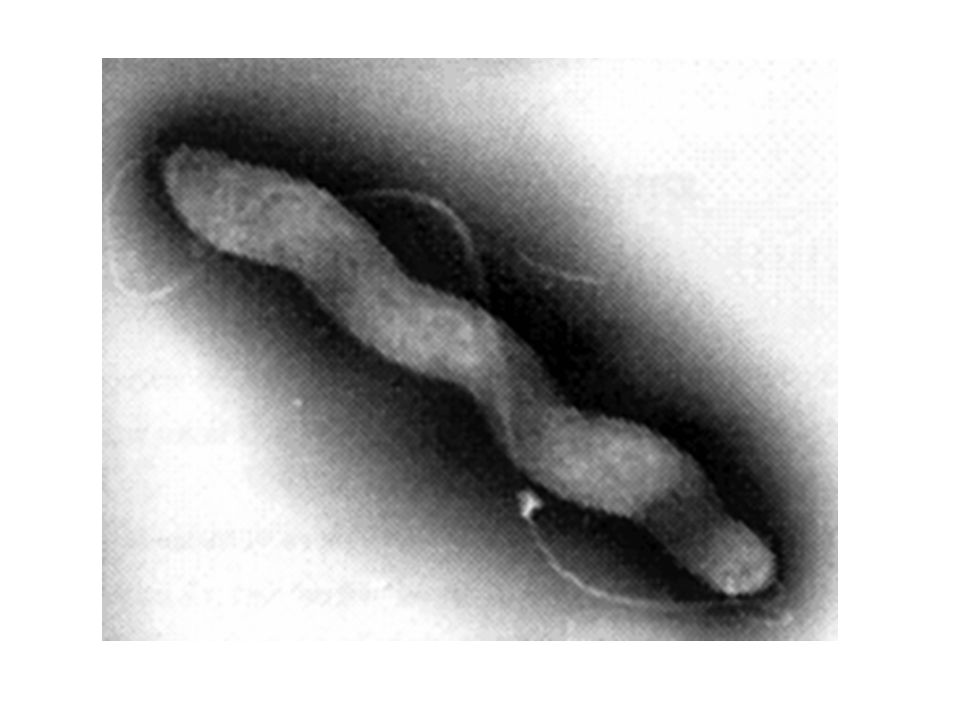

Кампилобактер фетус: патогенез и инфекции